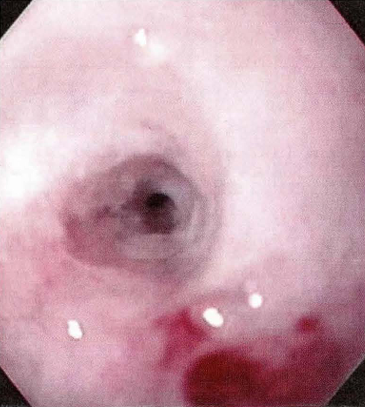

![]() | 내시경이 잘 통과 못하고 턱 막힘. 그러다가 점막이 벗겨져 출혈 발생. |